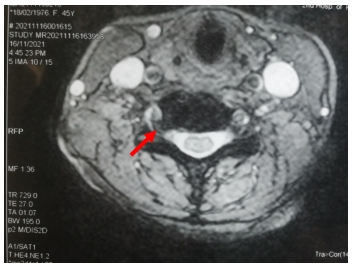

颈椎MRI示颈5-颈6椎间盘突出,压迫相应硬膜囊和神经根(红色箭头表示突出的间盘)

入院后王女士进行了全面检查,影像学结果显示患者第5-第6颈椎间盘突出特别明显,符合手术指征。综合考虑患者的病情和她对传统开放手术的抗拒,王新涛与患者及家属充分沟通后,决定为王女士做微创“钥匙孔手术”——颈椎后路脊柱内镜下颈椎管减压髓核摘除射频消融术。